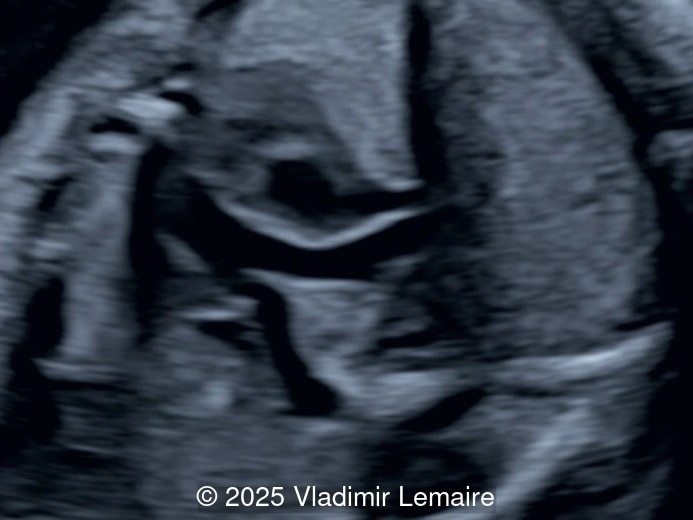

We present a case of isolated tricuspid atresia type 1 with persistent left superior vena cava. No other extracardiac anomalies were found. Our diagnosis was confirmed after birth.

In the images below, the abbreviations are as follows: RA: right atrium; RV: right ventricle; LV: left ventricle; MV: mitral valve; LA: left atrium; FO: foramen ovale; SVC: superior vena cava; LSVC: left superior vena cava; PV: pulmonary veins; PA: pulmonary artery; MPA: main pulmonary artery; RPA: right pulmonary artery; AO: aorta; dAO: descending aorta; aAO: ascending aorta; DA: ductus arteriosus; T: trachea; * marks the ventricular septal defect.

The four-chamber view in tricuspid atresia is diagnostic. It reveals a small right ventricle, a ventricular septal defect, and the absence of a right-sided atrioventricular junction. The size of the right ventricle mainly depends on the size of the ventricular septal defect: the smaller the ventricular septal defect, the smaller the right ventricle. Its contractility is normal with no myocardial thickening. The atretic tricuspid valve appears as echogenic thickened tissue and the right atrium is slightly dilated. The interatrial communication is large and there is often a redundant flap of the septum secundum that bulges into the left atrium. The interatrial and interventricular septa are malaligned.

The size of the great vessel arising from the right ventricle should be evaluated for the presence of stenosis, which is a common association. The severity of right outflow tract obstruction directly correlates with the size of the right ventricle and the ventricular septal defect. Occasionally, pulmonary or aortic atresia can be found.